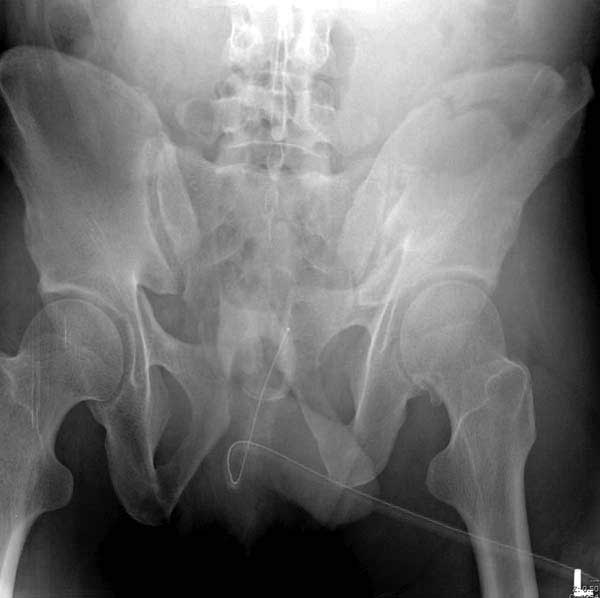

Здесь представлен случай 38 летнего больного (падение с высоты 9 метров) с нарушением тазового кольца. При поступлении для стабилизации передне-нижний аппарат наружной фиксации и на 6й день, вчера, операция из двух доступов.

Наружные фиксаторы создают не только стабильность костей таза, а также в экстренных случаях помогают уменьшить обьем таза в профилактике кровотечения!

Представлены снимки техники проведения стержней. Через место прикрепления прямой мышцы в Inferior Iliac Spine в направления вырезки создается жесткость. Weber clamp изнутри таза для репозиции, и фиксация после репозиции перелома крыла подвздошной кости. Наружный аппарат удален, нагрузка предполагается через два месяца.